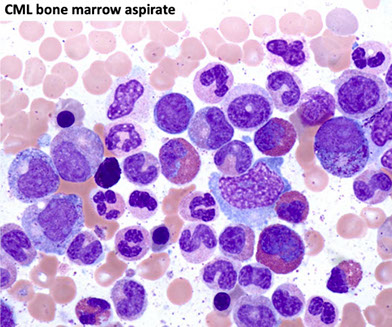

Marked myeloid hyperplasia with “myelocyte bulge”.

BM Findings

- markedly hypercellular (~100% cellularity)

- markedly elevated M:E ratio

Megakaryocytic hyperplasia and clustering.

-- "Dwarf mgkcs" - lots o small hypolobated megs

Myelodysplasia is not a major feature.

Marrow fibrosis (reticulin fibrosis) is variable